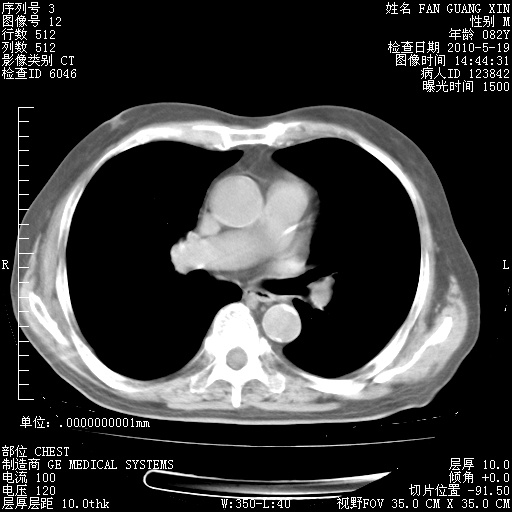

复查肺部CT,明显好转。为什么发热呢?

治疗3周后的肺部CT

治疗3周后的肺部CT纵隔窗